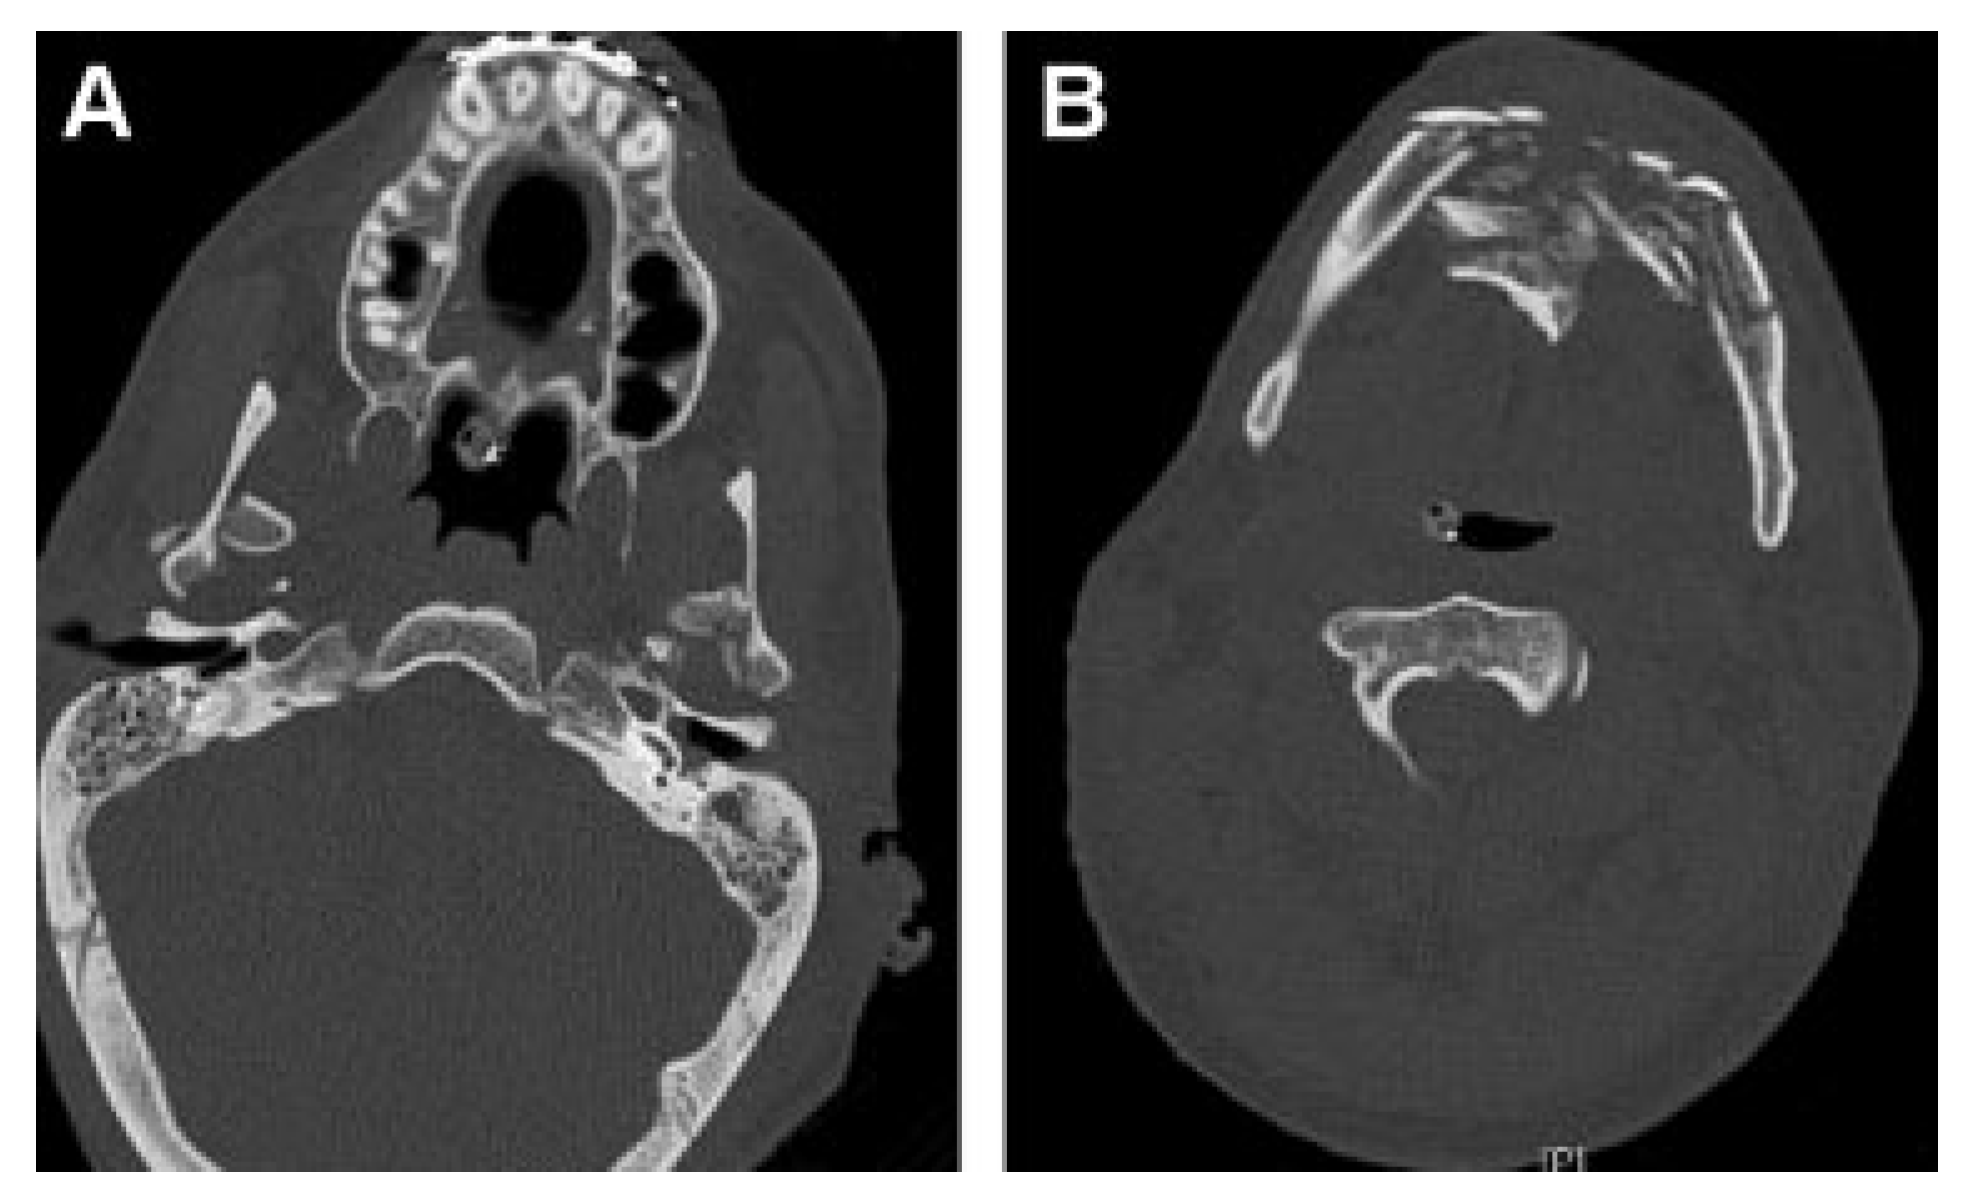

Figure 12.

(A,B) Computed tomography scans show comminuted anterior mandibular and bilateral condylar fractures. Fractures were stabilized with MMF for 12 weeks. (Images are courtesy of Colonel Robert Hale.) MMF, maxillomandibular fixation.

Patient 4 arrived in critical condition at BAMC 3 days after injury. He remained in serious condition for 5 months with his burn injuries constantly threatening his life. During this period and immediately afterward he underwent multiple burn, orthopedic, and general surgery procedures. Because of the severity and extent of his facial burn injuries, which limited conventional surgical approaches, reconstruction of his facial fractures was delayed. The patient remained in MMF for 12 weeks.

Nine months after injury, Patient 4 complained of drooling and difficulty eating. CT images revealed malunion of the anterior mandible fracture and bilateral bony ankylosis of craniomandibular articulations (Figure 13A,B). The patient also had lower lid ectropions, lower lip eversion, microstomia, chin ptosis, and lip incompetence secondary to burn scar contracture and malunion of the anterior mandible (Figure 13C–E).

Figure 13.

Nine months after injury. (A,B) Mandibular ankylosis and malunion are apparent. (C–E) Severe contractures, hypertrophic scars, ectropion, lip retraction, microstomia, and limited range of motion are directly related to burns and mandibular fractures. (Images are courtesy of Colonel Robert Hale).